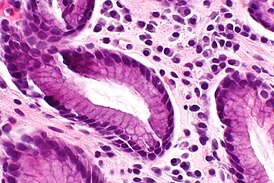

Гастри́т хрони́ческий (лат. gastritis, от др.-греч. γαστήρ [gaster] «желудок» + суффикс -itis «воспаление») — рецидивирующее, продолжительное по времени заболевание слизистой оболочки желудка воспалительного характера, протекающее с её структурными изменениями, такими как воспаление, нарушение клеточного обновления (регенерации), дистрофия и атрофия. Оно проявляется расстройством секреторной, моторной и инкреторной функций желудка[1]. В фазе ремиссии местные признаки воспаления отсутствуют, но в фазе обострения заболевания рецидивируют.